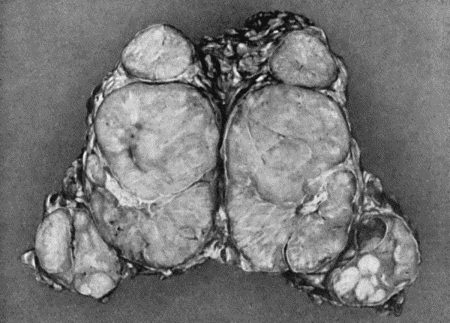

| 54. | Fibro-myoma of Uterus | 196 |

| 114. | Section through Gouty Bursa | 428 |